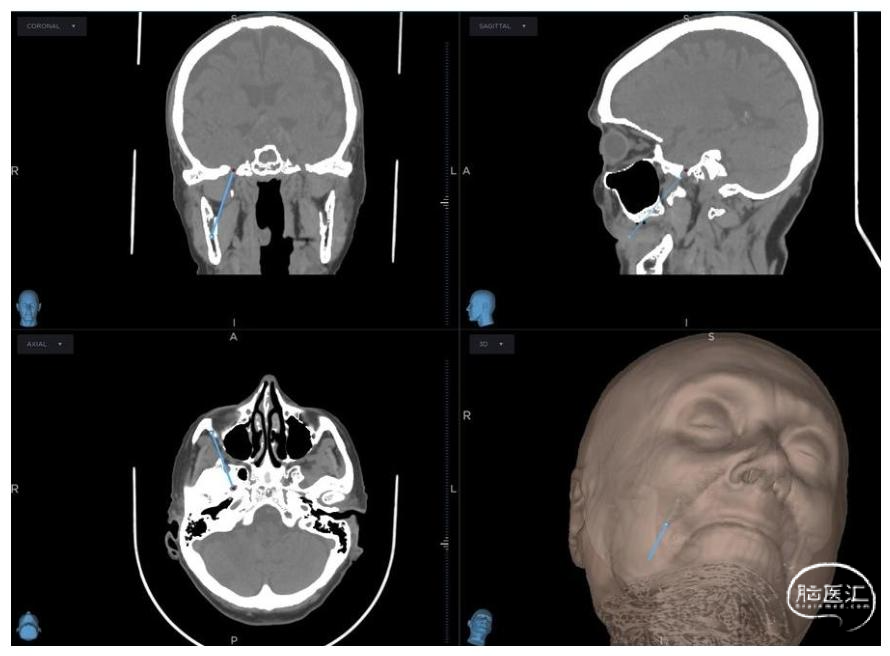

1.术前规划:术前1日,患者接受头颅及面颅薄层CT扫描,数据集导入StealthStation S8系统,术前完成靶向卵圆孔的穿刺针道设计(图1)。术者可识别解剖变异,并在必要时调整进针点,进针点可能偏离经典Hartel入路。

图1:经皮球囊压迫术的术前神经导航规划头颅CT图像,清晰显示靶向卵圆孔的预设穿刺针道(蓝线);三维表面重建可确认皮肤进针点相对于面部标志的位置,从而优化穿刺轨迹、避免骨质碰撞。